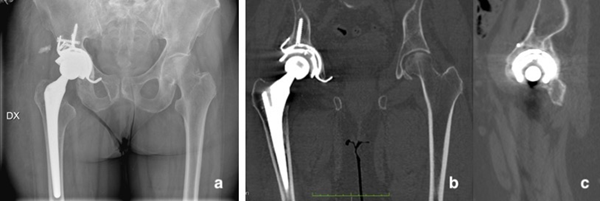

5:(a)術(shù)后3個月骨盆的AP射線照相和(b,c)骨盆的CT掃描顯示出良好的植入物定位和完全的骨折愈合。

對骨盆和術(shù)后右髖部進(jìn)行的X射線照相顯示,植入物“定位良好且固定”。三個月后,對患者的骨盆進(jìn)行了CT掃描,結(jié)果顯示“小梁杯骨融合”并“形成了愈傷組織”,完成了骨折愈合。使用DICOM圖像構(gòu)建的3D數(shù)字模型證實了這一點。